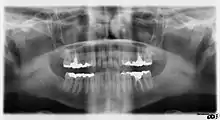

Галерея

Панорамная рентгенограмма показывает нижние зубы мудрости с горизонтальным ретинированием.